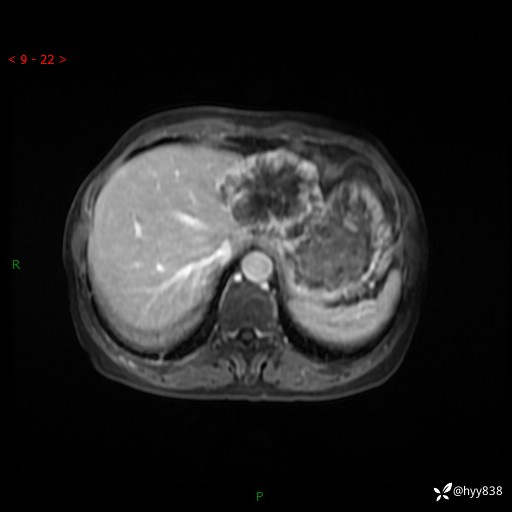

老年女性,偶然发现肝脏占位,综合各个序列,你考虑什么---结果公布

患者年龄:66岁

主诉:发现肝脏占位性病变2天

简要病史:患者2天前因“腰疼”至当地医院就诊时发现肝脏左叶占位性病变,无发热、畏寒,无皮肤黄染,无腹痛、腹泻,无恶心、呕吐、厌油等不适,今进一步诊治遂来我院就诊,门诊以“肝脏占位性病变性质待查”收入我科。 起病以来,患者精神、睡眠一般,饮食欠佳,二便正常,体力、体重无明显减轻,

辅助检查:MRI

临床诊断:肝占位

肝脏MRI平扫(同反相位)

T2WIfs+DWI

增强(动脉期+静脉期+延迟期)